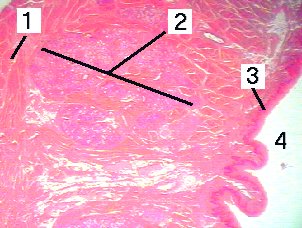

2. Mixed glands of Nuhn

3. Unkeratinized stratified squamous epithelium

4. Inferior surface

| Fig 7-001 | |

|---|---|

|

This is a very low magnification of a section throug the tongue. |

|

|

1. Skeletal muscle 2. Mixed glands of Nuhn 3. Unkeratinized stratified squamous epithelium 4. Inferior surface |